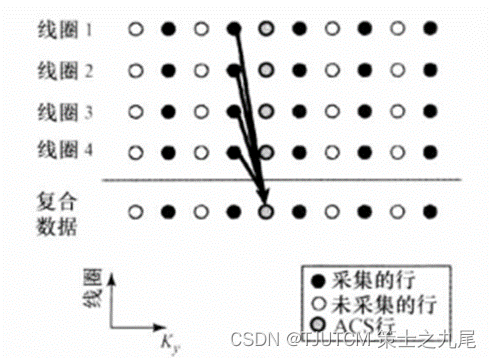

AUTO-SMASH和VD-AUTO-SMASH的K空间ACS行数据重建机制,从多线圈测量行数据合成全视野的符合校正行数据(此例中采集的4行数据用于拟合出覆盖全视野的复合数据)。

GRAPPA的K空间ACS行数据重建机制,阵列中各个线圈中采集的多块测量行被拟合到阵列中一个单线圈中采集的ACS行(此例中采集的4行数据用于拟合进4号线圈中一个单ACS行,各个圈代表在单一单线圈中采集的数据行)。